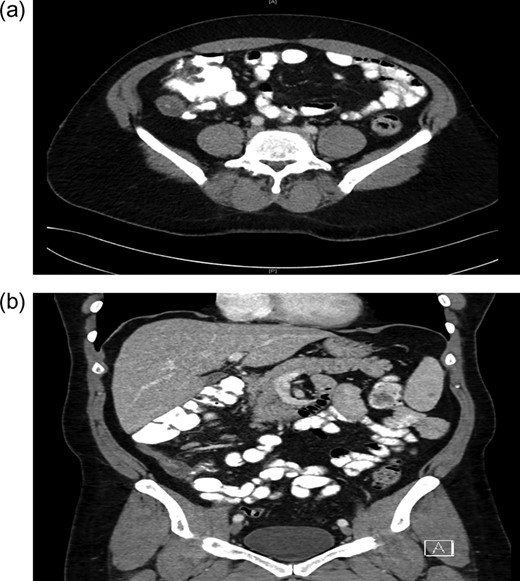

A 50-year-old male, with an unremarkable medical and surgical history, presented to the emergency department with a complaint of abdominal pain for 10 days. The pain started in right iliac fossa and was localized. It was associated with anorexia, nausea and fever 1 day prior to his presentation. The pain was aggravated by movement and relieved by simple analgesia. There was no history of vomiting, changes in bowel habits, or recent weight loss. On examination, the patient was looking healthy and was afebrile. The abdomen had minimal tenderness over the right iliac fossa with an absence of any other signs of acute appendicitis. Laboratory investigations were within normal limits. The Emergency Department physicians examined the patient initially and their impression was an atypical presentation of acute appendicitis. A computerized tomography (CT) scan of the abdomen was done and indicated a well-circumscribed hypodense lesion at the base of the appendix, measuring 2.6 × 2.4 cm2, with no calcification or abnormal enhancement. The distal part of the appendix was dilated, measuring 8 mm in diameter with no surrounding fat stranding or significantly enlarged lymph nodes (Fig. 1).

(a) Computed tomography of the axial view of abdomen showing mass in base of appendix. (b) Computed tomography of the coronal view of abdomen showing mass in base of appendix.